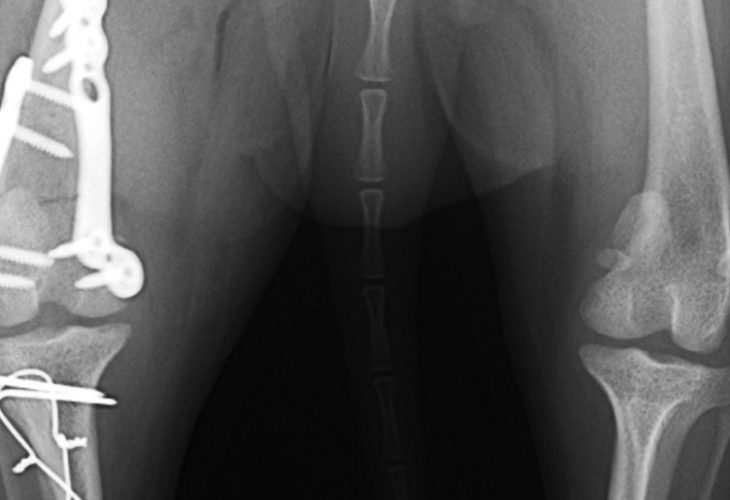

極小若齢犬橈尺骨骨折

大腿骨骨折+膝蓋骨内方脱臼整復

左右橈尺骨横骨折